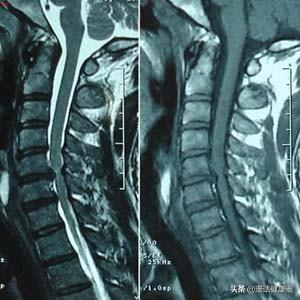

Mauvaise posture ou blessure sportive, entraînant une spondylose cervicale par redressement de la courbure physiologique de la colonne vertébrale.

Vu de l'extérieur, le cou humain semble droit, alors qu'en réalité la colonne cervicale est courbée. Notre colonne vertébrale n'est pas droite mais en forme de S avec quatre courbures physiologiques, convexe en avant dans le cou et la région lombaire et convexe en arrière dans les régions thoracique et sacrée, ce qui permet une meilleure mobilité et une meilleure fonction de port de poids de la colonne vertébrale.

La tête baissée à long terme pour jouer au téléphone portable, la colonne cervicale sera en état de flexion à long terme, il est facile de conduire à la colonne cervicale autour des muscles et des ligaments en raison de l'étirement et de la relaxation excessifs, pour maintenir la stabilité de la fonction de la colonne cervicale diminue, à long terme la colonne cervicale courbure physiologique de la colonne cervicale se redresser, la colonne cervicale à long terme pour supporter le fardeau d'un plus grand, couplé avec la colonne cervicale des disques à partir de l'âge de 20 ans après le début de la dégénérescence de la colonne cervicale, il est facile de déclencher une hernie discale, comme la maladie de la colonne vertébrale forte se produit.